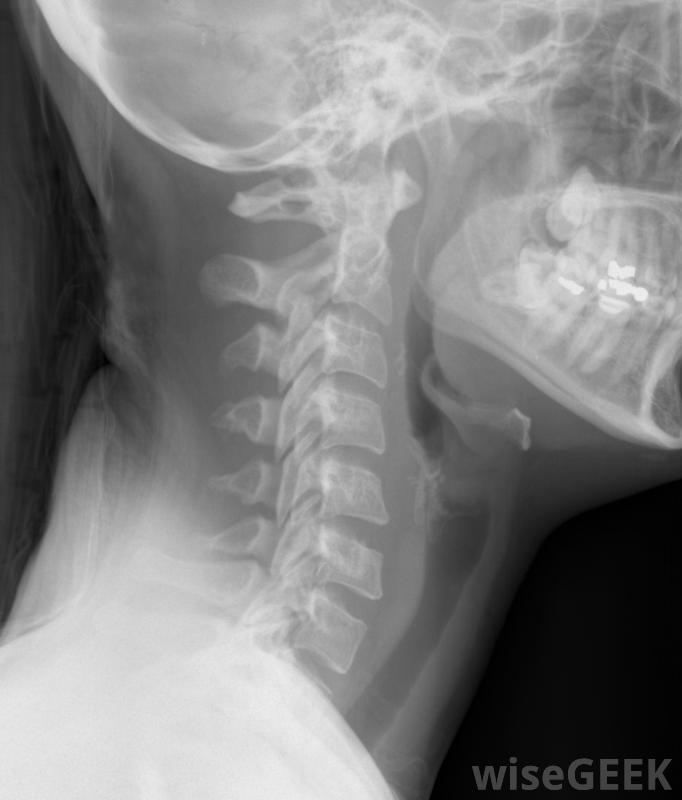

颈部X光片,包括颈椎通过颈部的前部或前部或后部,或颈部的后部进入脊柱。通常情况下,一个或多个椎间盘已被移除,开始进行颈椎融合术。这包括从人体供者处取骨,